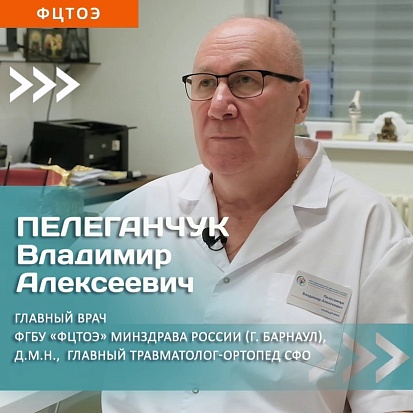

ФЕДЕРАЛЬНЫЙ ЦЕНТР ТРАВМАТОЛОГИИ, ОРТОПЕДИИ И ЭНДОПРОТЕЗИРОВАНИЯ

Факторы достижения исторического максимума 2023